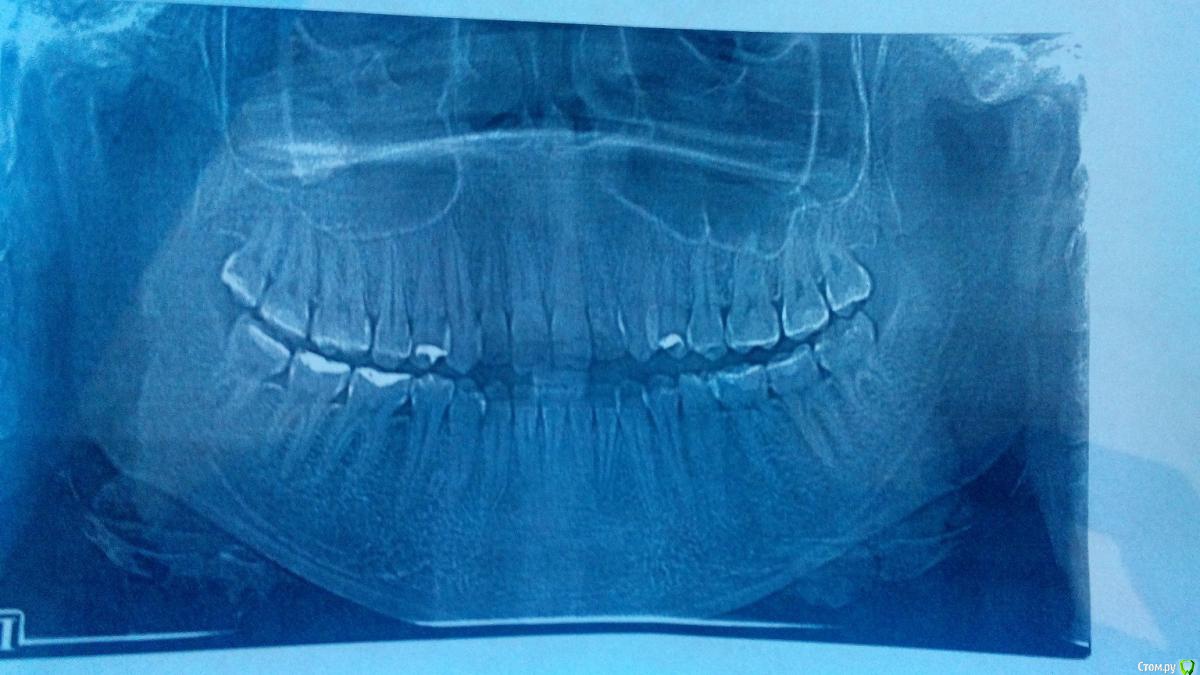

Ситуация следующая,в сентябре сделала снимки и ортодонт сказал,что головка сустава смещена

сегодня 12 декабря сделала опг снова,к сожалению сустав там плохо,как мне кажется

хотелось бы услышать ваши мнения,уважаемые врачи

возможно ли довести до нормального состояния прикус,зубы без операции??

так же интересует удаление восьмых зубов в моем случае ,так как один хирург сказал,что отказывается удалять мне правую восьмерку ( а с суставом проблема к слову справа) ,так как повредит мне